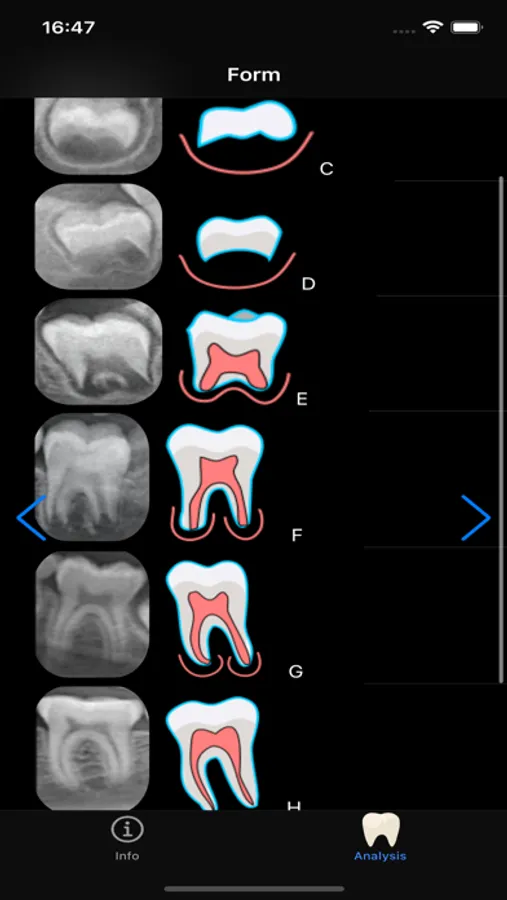

This app utilizes Demirjian's system for dental age estimation. The system can be used to estimate the dental age of children between 3 and 16 years old. Panoramic radiograph is necessary to identify the developmental stages of the seven mandibular teeth on the left side (excluding third molars). In case of tooth agenesis or tooth loss in the left side of the mandible, the contralateral tooth in the right side should be considered.